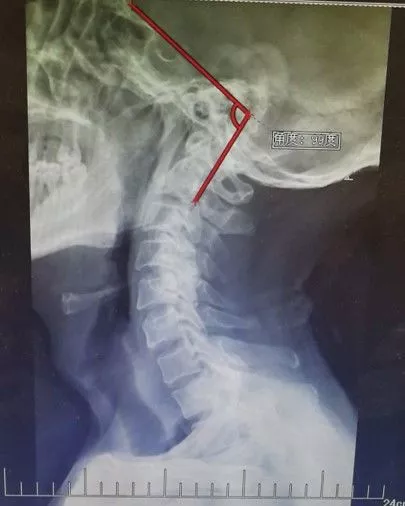

男性,59岁,半年前无诱因出现右半身麻木,伴右侧肢体乏力,右胸壁多汗,行走后右下肢抽痛明显,于当地医院就诊,查颈椎+胸椎+腰椎MRI示“颈髓脊髓空洞,腰4-5椎间盘突出”,对症治疗后症状无明显缓解。现为求进一步诊治,来西安交通大学第一附属医院,门诊以“脊髓空洞”收住入院。

影像学资料

1. Chiairi畸形并颈髓空洞

2. 脊柱侧弯